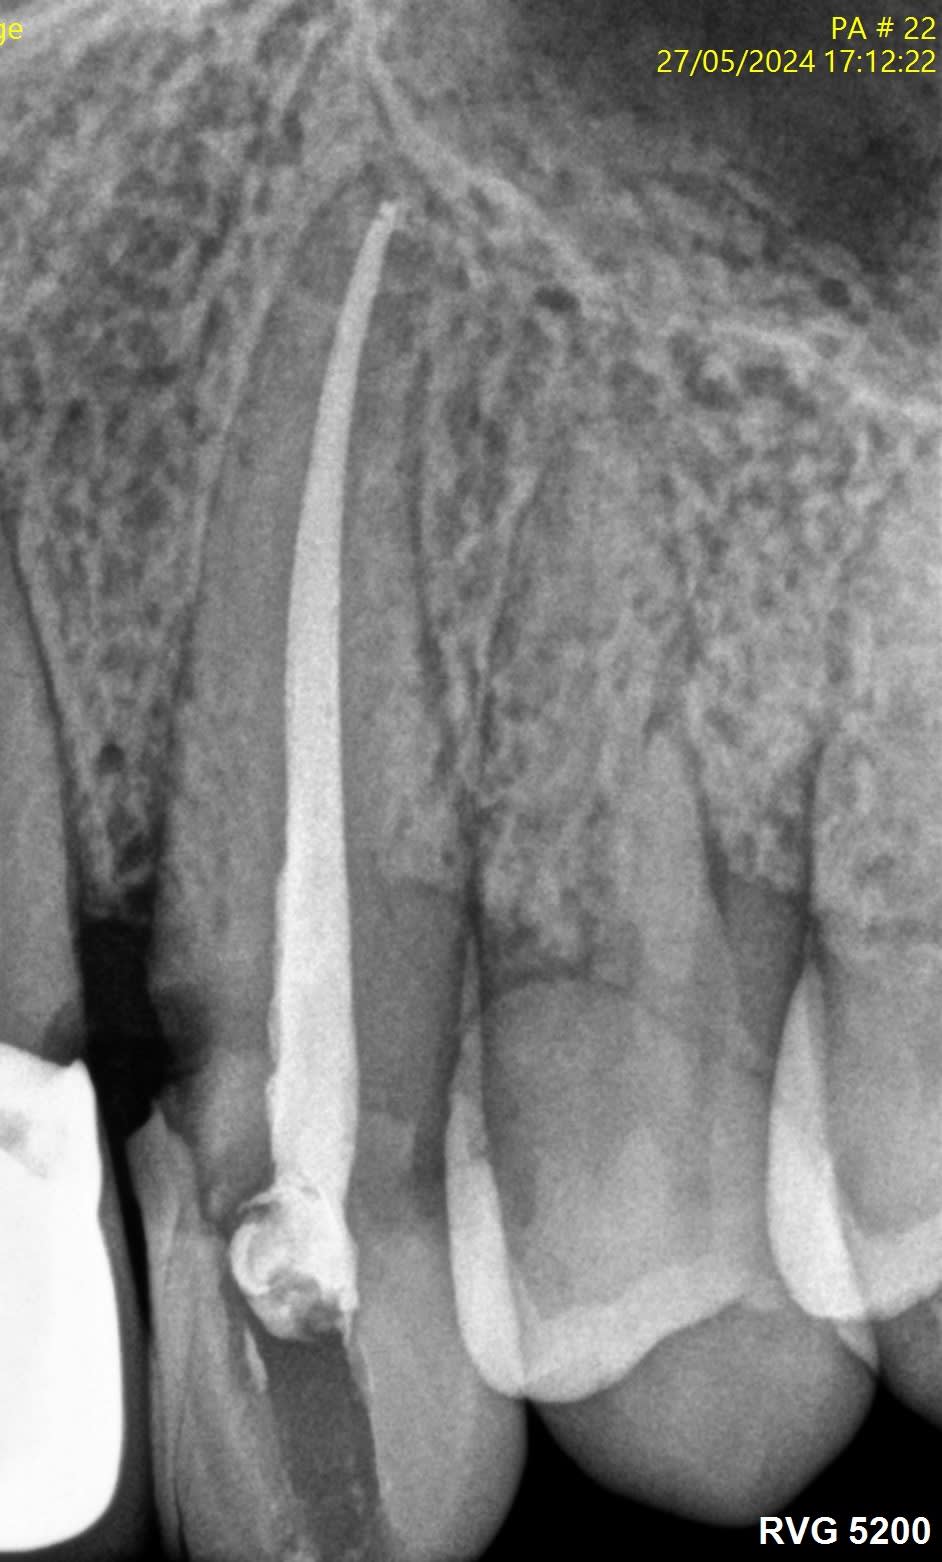

Voici quelques radio pour illustrer...

Préparation du canal en R25 avec localisateur interféré, rinçage tous les 2/3 passages (hypo 3% megadental) + lime permeab (en passant le foramen)

Bien souvent, j'arrive à l'apex et au dernier appui le localisateur bip en continu et le moteur fait demi tour.. Ai-je déchiré mon apex et cela me vaut les suites post op? le phénomène est ultra léger je n'y vais pas comme un bourrin !!

Je jauge mon foramen et ajuste le cône.

Ciment AH+ et condensation verticale à chaud.